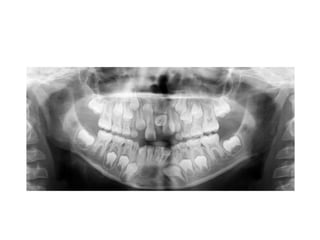

RADIOLOGIAORTOPANTOMOGRAFIA